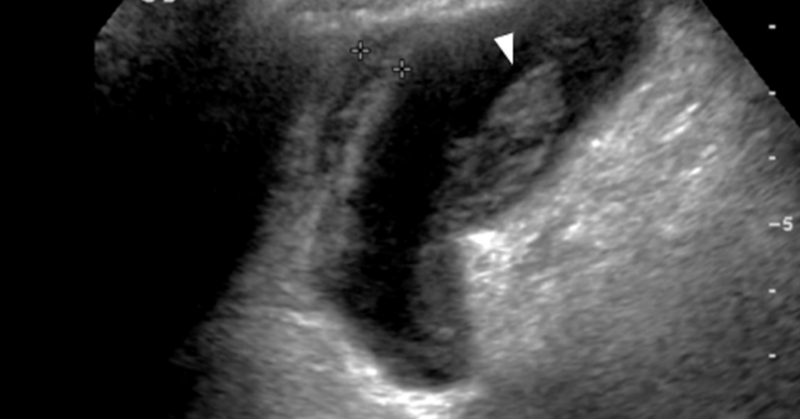

Challenge yourself with a case brought to you by Malak Itani, MD @ItaniMalak from @WashUMedMIR: 70M with RUQ pain x 1 week with nodular thickening of the GB wall, superimposed on changes of cholecystitis on initial CT, s/p cholecystostomy tube on MR.

Axial and coronal contrast enhanced CT images demonstrating: Multiple discrete and confluent areas of cystic change within the gallbladder wall which is markedly thickened, continuous enhancement of the mucosa and serosa Answer: Xanthogranulomatous cholecystitis